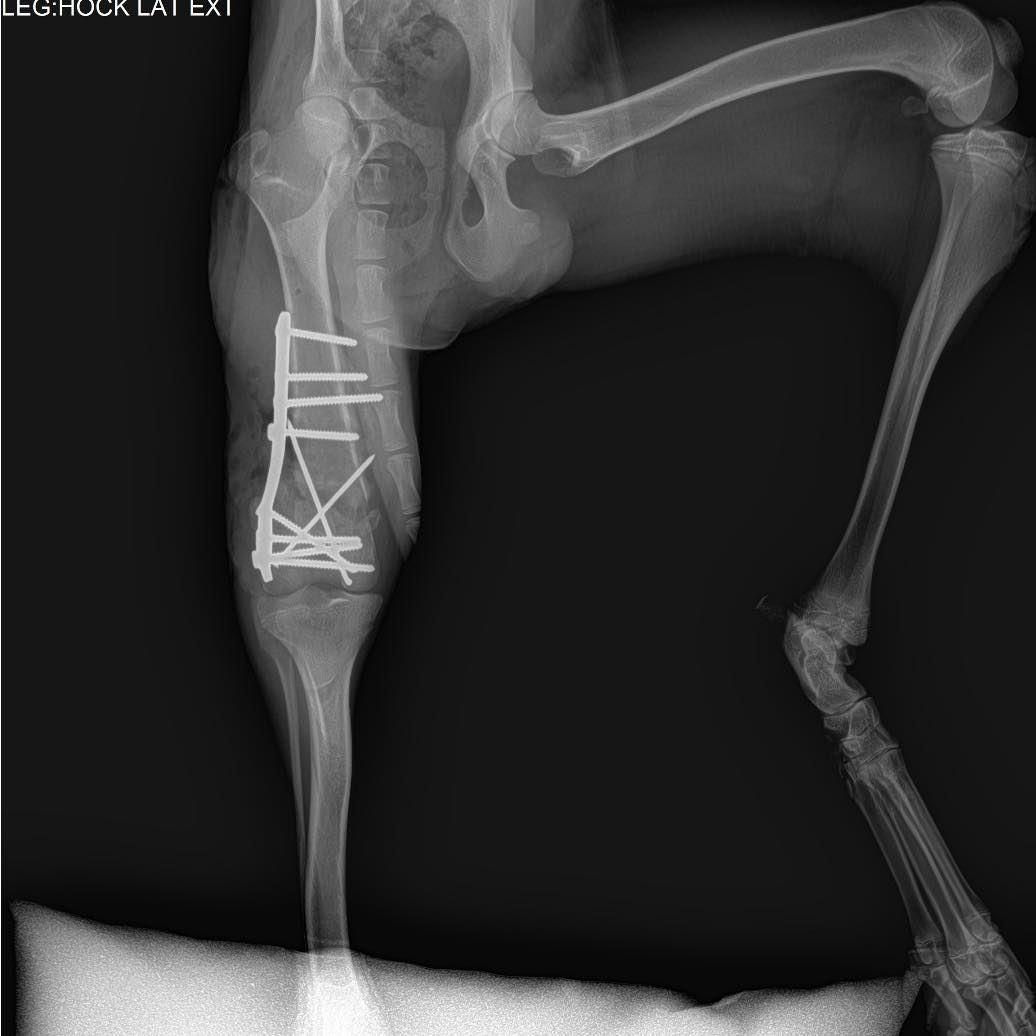

๐Ÿพ ๐Œ๐ˆ๐“๐’๐ˆ๐’ โ€“ ๐จ๐ฎ๐ซ ๐›๐ซ๐š๐ฏ๐ž, ๐ก๐š๐ฉ๐ฉ๐ฒ-๐ ๐จ-๐ฅ๐ฎ๐œ๐ค๐ฒ ๐›๐จ๐ฒ ๐ฅ๐จ๐จ๐ค๐ข๐ง๐  ๐Ÿ๐จ๐ซ ๐ก๐ข๐ฌ ๐Ÿ๐จ๐ซ๐ž๐ฏ๐ž๐ซ ๐Ÿ๐š๐ฆ๐ข๐ฅ๐ฒ ๐Ÿพ This handsome ๐€๐ซ๐ข๐ž๐ ๐ž๐จ๐ข๐ฌ ๐œ๐ซ๐จ๐ฌ๐ฌ, almost 1.5 years old, has come such a long way. ๐Ÿ’ช When Mitsis arrived to us back in June, he was limping badly โ€” X-rays revealed his bone was completely broken and dangling. ๐Ÿ’” But thanks to a skilled orthopedic surgeon (and lots of love!), he underwent a successful operation and began his healing journey. ๐Ÿฉบ (See X-rays) After months of rest and limited movement, Mitsis is now stretching his legs again โ€” literally! ๐Ÿ•๐Ÿ’จ Heโ€™s gaining strength every day, playing with his doggy friends, and showing everyone just how joyful and resilient he is. Mitsis is ๐Ÿ๐š๐ง๐ญ๐š๐ฌ๐ญ๐ข๐œ ๐ฐ๐ข๐ญ๐ก ๐จ๐ญ๐ก๐ž๐ซ ๐๐จ๐ ๐ฌ, loves having playmates, and equally adores ๐œ๐ฎ๐๐๐ฅ๐ž๐ฌ ๐Ÿ๐ซ๐จ๐ฆ ๐ก๐ข๐ฌ ๐ก๐ฎ๐ฆ๐š๐ง๐ฌ. Heโ€™s social, gentle, and full of love โ€” ready to bring happiness to his new home. โค๏ธ ๐ŸŽถMitsis even joined us at an event full of people, music, and excitement โ€” and he handled it like a pro! Nothing phased him; he stayed calm, friendly, and curious the entire time. ๐ŸŒŸ ๐Ÿก He can be adopted Cyprus or UK โธป ๐Ÿพ ฮœฮฏฯ„ฯƒฮทฯ‚ โ€“ ฯ„ฮฟ ฮณฮตฮฝฮฝฮฑฮฏฮฟ, ฯ‡ฮฑฯฮฟฯฮผฮตฮฝฮฟ ฮฑฮณฯŒฯฮน ฮผฮฑฯ‚ ฯ€ฮฟฯ… ฯˆฮฌฯ‡ฮฝฮตฮน ฯ„ฮทฮฝ ฯ€ฮฑฮฝฯ„ฮฟฯ„ฮนฮฝฮฎ ฯ„ฮฟฯ… ฮฟฮนฮบฮฟฮณฮญฮฝฮตฮนฮฑ! ๐Ÿพ ฮ‘ฯ…ฯ„ฯŒ ฯ„ฮฟ ฯ€ฮฑฮฝฮญฮผฮฟฯฯ†ฮฟ ๐€๐ซ๐ข๐ž๐ ๐ž๐จ๐ข๐ฌ ๐œ๐ซ๐จ๐ฌ๐ฌ, ฯƒฯ‡ฮตฮดฯŒฮฝ 1,5 ฮญฯ„ฮฟฯ…ฯ‚, ฮญฯ‡ฮตฮน ฮดฮนฮฑฮฝฯฯƒฮตฮน ฮผฮนฮฑ ฮฑฯ€ฮฏฯƒฯ„ฮตฯ…ฯ„ฮท ฮดฮนฮฑฮดฯฮฟฮผฮฎ. ๐Ÿ’ช ฮŒฯ„ฮฑฮฝ ฮฎฯฮธฮต ฯƒฮต ฮตฮผฮฌฯ‚ ฯƒฯ„ฮนฯ‚ ฮฑฯฯ‡ฮญฯ‚ ฯ„ฮฟฯ… ฮ™ฮฟฯ…ฮฝฮฏฮฟฯ…, ฮบฮฟฯ…ฯ„ฯƒฯŒฯ‚ โ€” ฮฟฮน ฮฑฮบฯ„ฮนฮฝฮฟฮณฯฮฑฯ†ฮฏฮตฯ‚ ฮญฮดฮตฮนฮพฮฑฮฝ ฯŒฯ„ฮน ฯ„ฮฟ ฮบฯŒฮบฮฑฮปฮฟ ฯ„ฮฟฯ… ฮฎฯ„ฮฑฮฝ ฯ„ฮตฮปฮตฮฏฯ‰ฯ‚ ฯƒฯ€ฮฑฯƒฮผฮญฮฝฮฟ ฮบฮฑฮน ฮบฯฮตฮผฯŒฯ„ฮฑฮฝ. ๐Ÿ’” ฮงฮฌฯฮท ฯŒฮผฯ‰ฯ‚ ฯƒฮต ฮญฮฝฮฑฮฝ ฮฟฯฮธฮฟฯ€ฮตฮดฮนฮบฯŒ (ฮบฮฑฮน ฮผฮต ฯ€ฮฟฮปฮปฮฎ ฮฑฮณฮฌฯ€ฮท), ฯ…ฯ€ฮฟฮฒฮปฮฎฮธฮทฮบฮต ฯƒฮต ฮตฯ€ฮนฯ„ฯ…ฯ‡ฮทฮผฮญฮฝฮท ฮตฯ€ฮญฮผฮฒฮฑฯƒฮท ฮบฮฑฮน ฮพฮตฮบฮฏฮฝฮทฯƒฮต ฯ„ฮฟ ฯ„ฮฑฮพฮฏฮดฮน ฯ„ฮทฯ‚ ฮฑฮฝฮฌฯฯฯ‰ฯƒฮฎฯ‚ ฯ„ฮฟฯ…. ๐Ÿฉบโœจ (ฮ”ฮตฮฏฯ„ฮต ฯ„ฮนฯ‚ ฮฑฮบฯ„ฮนฮฝฮฟฮณฯฮฑฯ†ฮฏฮตฯ‚) ฮœฮตฯ„ฮฌ ฮฑฯ€ฯŒ ฮผฮฎฮฝฮตฯ‚ ฯ€ฮตฯฮนฮฟฯฮนฯƒฮผฮฟฯ ฮบฮฑฮน ฮพฮตฮบฮฟฯฯฮฑฯƒฮทฯ‚, ฮฟ ฮœฮนฯ„ฯƒฮฎฯ‚ ฯ„ฯŽฯฮฑ ฮพฮฑฮฝฮฑฮฝฮฟฮฏฮณฮตฮน ฯ„ฮฑ ฯ†ฯ„ฮตฯฮฌ ฯ„ฮฟฯ… โ€” ฮฎ ฮผฮฌฮปฮปฮฟฮฝ ฯ„ฮฑ ฯ€ฯŒฮดฮนฮฑ ฯ„ฮฟฯ…! ๐Ÿ•๐Ÿ’จ ฮ”ฯ…ฮฝฮฑฮผฯŽฮฝฮตฮน ฮบฮฑฮธฮทฮผฮตฯฮนฮฝฮฌ, ฯ€ฮฑฮฏฮถฮตฮน ฮผฮต ฯ„ฮฑ ฯƒฮบฯ…ฮปฮฟฯ†ฮนฮปฮฑฯฮฌฮบฮนฮฑ ฯ„ฮฟฯ… ฮบฮฑฮน ฮดฮตฮฏฯ‡ฮฝฮตฮน ฯƒฮต ฯŒฮปฮฟฯ…ฯ‚ ฯ€ฯŒฯƒฮฟ ฯ‡ฮฑฯฮฟฯฮผฮตฮฝฮฟฯ‚ ฮบฮฑฮน ฮฑฮฝฮธฮตฮบฯ„ฮนฮบฯŒฯ‚ ฮตฮฏฮฝฮฑฮน. ฮŸ ฮœฮนฯ„ฯƒฮฎฯ‚ ฮตฮฏฮฝฮฑฮน ฮบฮฑฮปฯŒฯ‚ ฮผฮต ฮฌฮปฮปฮฑ ฯƒฮบฯ…ฮปฮนฮฌ, ฮปฮฑฯ„ฯฮตฯฮตฮน ฮฝฮฑ ฮญฯ‡ฮตฮน ฯ€ฮฑฯฮญฮฑ ฮณฮนฮฑ ฯ€ฮฑฮนฯ‡ฮฝฮฏฮดฮน, ฮฑฮปฮปฮฌ ฮตฮพฮฏฯƒฮฟฯ… ฮฑฮณฮฑฯ€ฮฌ ฮบฮฑฮน ฯ„ฮฑ ฯ‡ฮฌฮดฮนฮฑ ฮบฮฑฮน ฯ„ฮนฯ‚ ฮฑฮณฮบฮฑฮปฮนฮญฯ‚ ฮฑฯ€ฯŒ ฯ„ฮฟฯ…ฯ‚ ฮฑฮฝฮธฯฯŽฯ€ฮฟฯ…ฯ‚ ฯ„ฮฟฯ…. ฮ•ฮฏฮฝฮฑฮน ฮบฮฟฮนฮฝฯ‰ฮฝฮนฮบฯŒฯ‚, ฮณฮปฯ…ฮบฯŒฯ‚ ฮบฮฑฮน ฮณฮตฮผฮฌฯ„ฮฟฯ‚ ฮฑฮณฮฌฯ€ฮท โ€” ฮญฯ„ฮฟฮนฮผฮฟฯ‚ ฮฝฮฑ ฮณฮตฮผฮฏฯƒฮตฮน ฯ‡ฮฑฯฮฌ ฯ„ฮฟ ฮฝฮญฮฟ ฯ„ฮฟฯ… ฯƒฯ€ฮฏฯ„ฮน. โค๏ธ ๐Ÿก ฮœฯ€ฮฟฯฮตฮฏ ฮฝฮฑ ฯ…ฮนฮฟฮธฮตฯ„ฮทฮธฮตฮฏ ฮšฯฯ€ฯฮฟ ฮฎ ฮ‘ฮณฮณฮปฮฏฮฑ